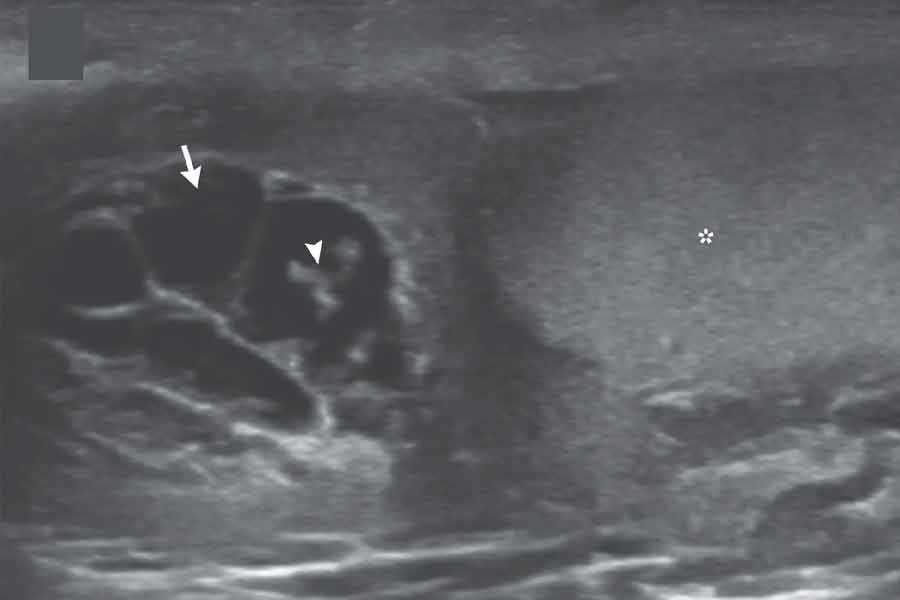

চিকিৎসকেরা জানিয়েছেন, গোপনাঙ্গের ব্যথা নিয়ে যখন ওই যুবক হাসপাতালে আসেন, তখন প্রাথমিক পরীক্ষায় দেখা যায়, যুবকের ডান দিকের অণ্ডকোষটি ফুলে রয়েছে। সঙ্গে রয়েছে ব্যথা ও জ্বর। তড়িঘড়ি আল্ট্রা সাউন্ড পরীক্ষা করার সিদ্ধান্ত নেন চিকিৎসকেরা। আর সেই পরীক্ষাতেই দেখা যায়, অণ্ডকোষের যে লসিকাবাহের মাধ্যমে দেহতরল ও শ্বেত রক্তকণিকা পরিবাহিত হয়, তাতে পোকার মতো দেখতে কিছু জিনিস নড়াচড়া করছে। আরও কিছু পরীক্ষার পর জানা যায়, ওই যুবক ‘লিম্ফ্যাটিক ফাইলেরিয়েসিস’ রোগে আক্রান্ত। চলতি ভাষায় একে গোদ বলে। ক্রান্তীয় ও নিরক্ষীয় অঞ্চলে মশার কামড়ের মাধ্যমে ছড়িয়ে পড়ে এই রোগ।

‘ফাইলেরিয়াল ডান্স’ সঙ্কেতের সেই ছবি।

কিন্তু পোকার নাচের মতো যে জিনিসটি দেখা যাচ্ছিল, সেটি কী? চিকিৎসকরা জানাচ্ছেন, একে ‘ফাইলেরিয়াল ডান্স’ সঙ্কেত বলে। জীবন্ত কৃমি লসিকাবাহের মধ্য দিয়ে দেহের বিভিন্ন অঙ্গে ছড়িয়ে পড়তে পারে। তার পর সেখানে এই জীবন্ত কৃমিগুলি কখনও নড়াচড়া করলে এমন ঘটনা ঘটে। চিকিৎসকরা জানাচ্ছেন, ওই যুবক অত্যন্ত ভাগ্যবান। খুব অল্পেই তাঁর রোগ ধরা পড়ে গিয়েছে। ৩ সপ্তাহ পরজীবীনাশক ওষুধ খাওয়ার পর অনেকটাই সুস্থ তিনি। পরবর্তী পরীক্ষায় আর কৃমির হদিস মেলেনি।